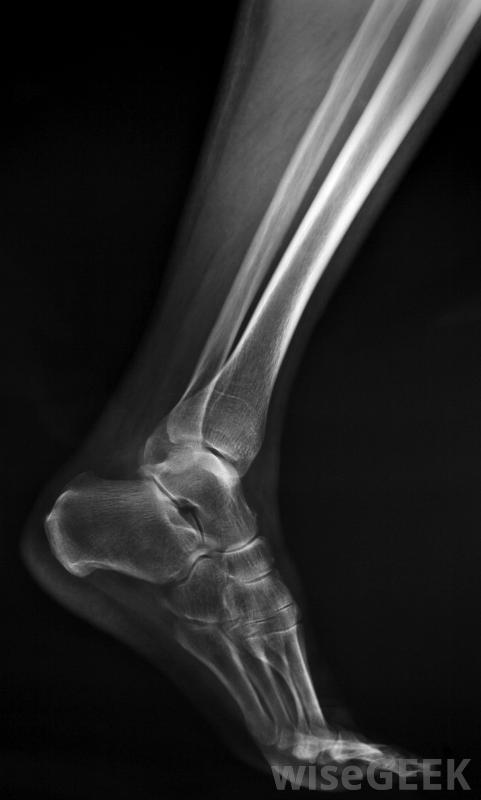

胫骨应力性骨折在跑步者中很常见。重复性胫骨过载和应力使其无法自然愈合并导致胫骨应力性骨折。由于反复的创伤,骨骼无法吸收冲击力,从而削弱了骨骼。诊断包括彻底的病史、体格检查和可能的骨骼扫描。X光通常不显示一种骨应力性骨折,尽管连续的X光片可以显示出骨骼试图愈合的部位。

X光片通常不会显示胫骨应力性骨折胫骨应力性骨折最常见的症状是胫骨下半部局部疼痛,与胫骨夹板疼痛相似它通常开始时是隐痛或轻微刺激,并随着持续使用腿部而逐渐加重,如步行、跑步或运动,疼痛逐渐加重。一般来说,胫骨疼痛在休息时消失,尽管情况严重,即使不使用腿也可以继续。在这种情况下,这种疼痛会严重到使人无法行走。胫骨应力性骨折的另一个症状是由于肌肉、肌腱发炎而沿胫骨肿胀,以及骨骼周围的组织。胫骨受到挤压时可能会受伤或骨折部位出现肌肉压痛。在某些情况下,胫骨应力性骨折也可能导致小腿疼痛或膝关节疼痛。有几种因素会导致胫骨应力性骨折的疼痛和其他症状。过度训练,如进行强度过大或过大的运动量,都会导致疼痛重复性压力导致胫骨损伤。营养不良和钙镁缺乏会导致骨骼健康状况不佳,并增加压力性骨折的风险。低水平的睾酮或雌激素也是危险因素,以及长期使用某些药物,如类固醇胫骨疼痛是胫骨应力性骨折最常见的症状。